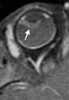

Globe calcification

Intraorbital calcification